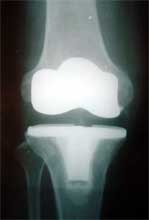

复合BMP的脱钙异体骨基质填充骨缺损      复合BMP的脱钙异体骨基质修复骨缺损,膝关节置换术后